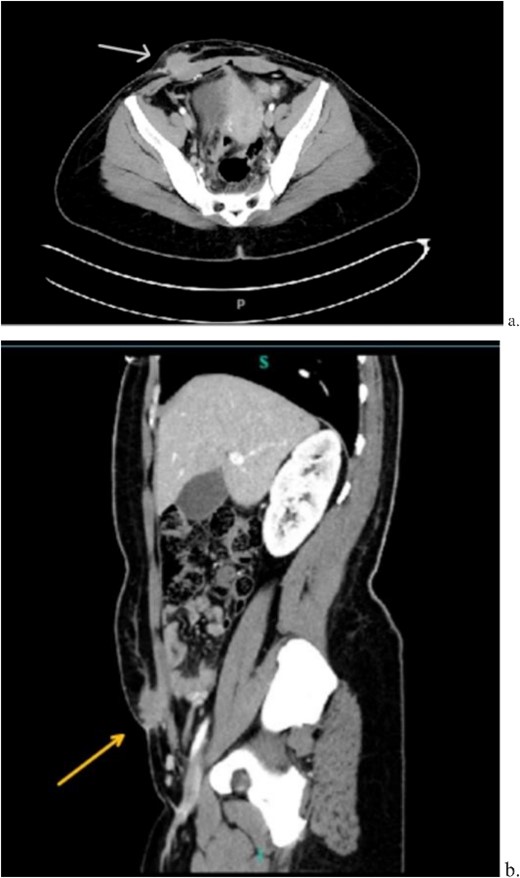

Computed tomography (CT) scan demonstrated a slightly larger, rounded mass with irregular, spiculated margins in the subcutaneous fat of the left ventral pelvis with fat stranding measuring 4.2 × 4.1 × 3.7 cm (Fig. 3). CT-guided biopsy of the mass was performed and revealed endometriosis. The decision was made to take the patient to the operating room for elective resection.

Computed tomography axial (a) and sagittal (b) views of a 4.2 × 4.1 × 3.7 cm enhancing, irregular mass on the abdominal wall (arrow) suggestive of AWE.